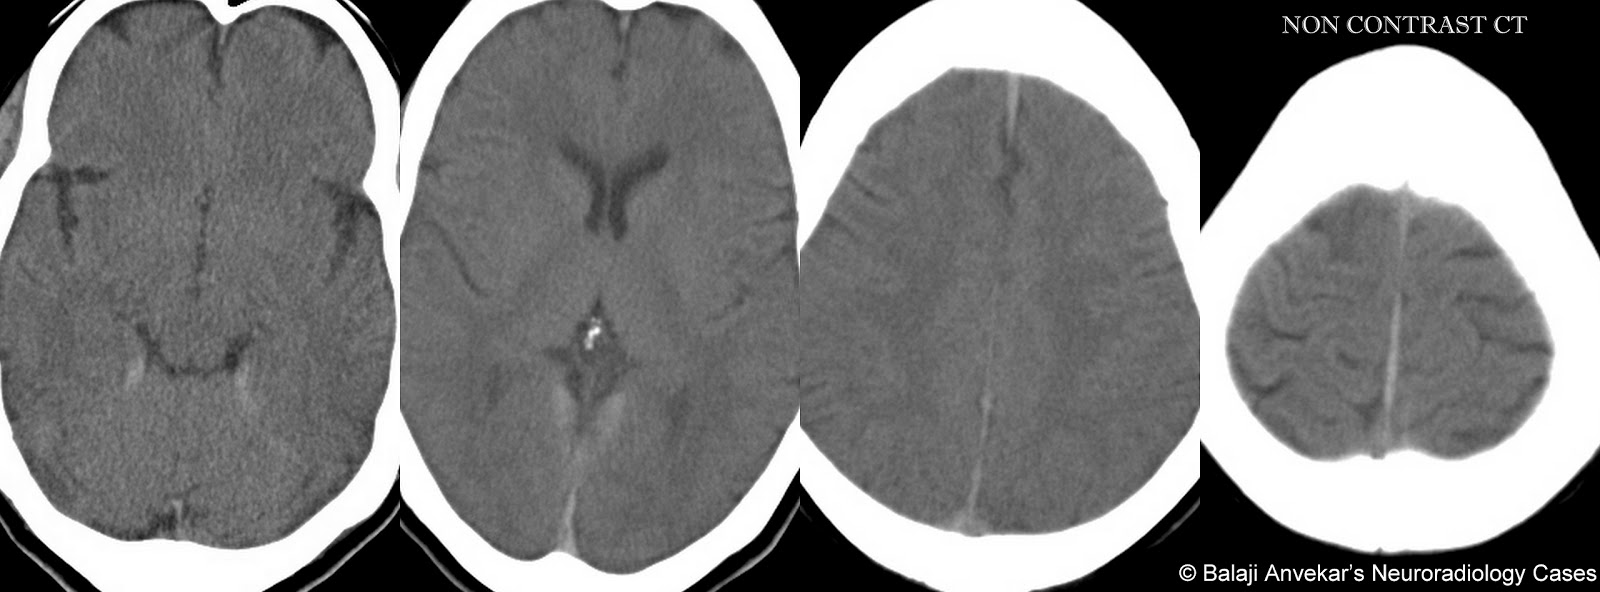

По мне гипертрофический спинальный пахименингит.

Легко:

А так выглядит пахименингит на КТ: